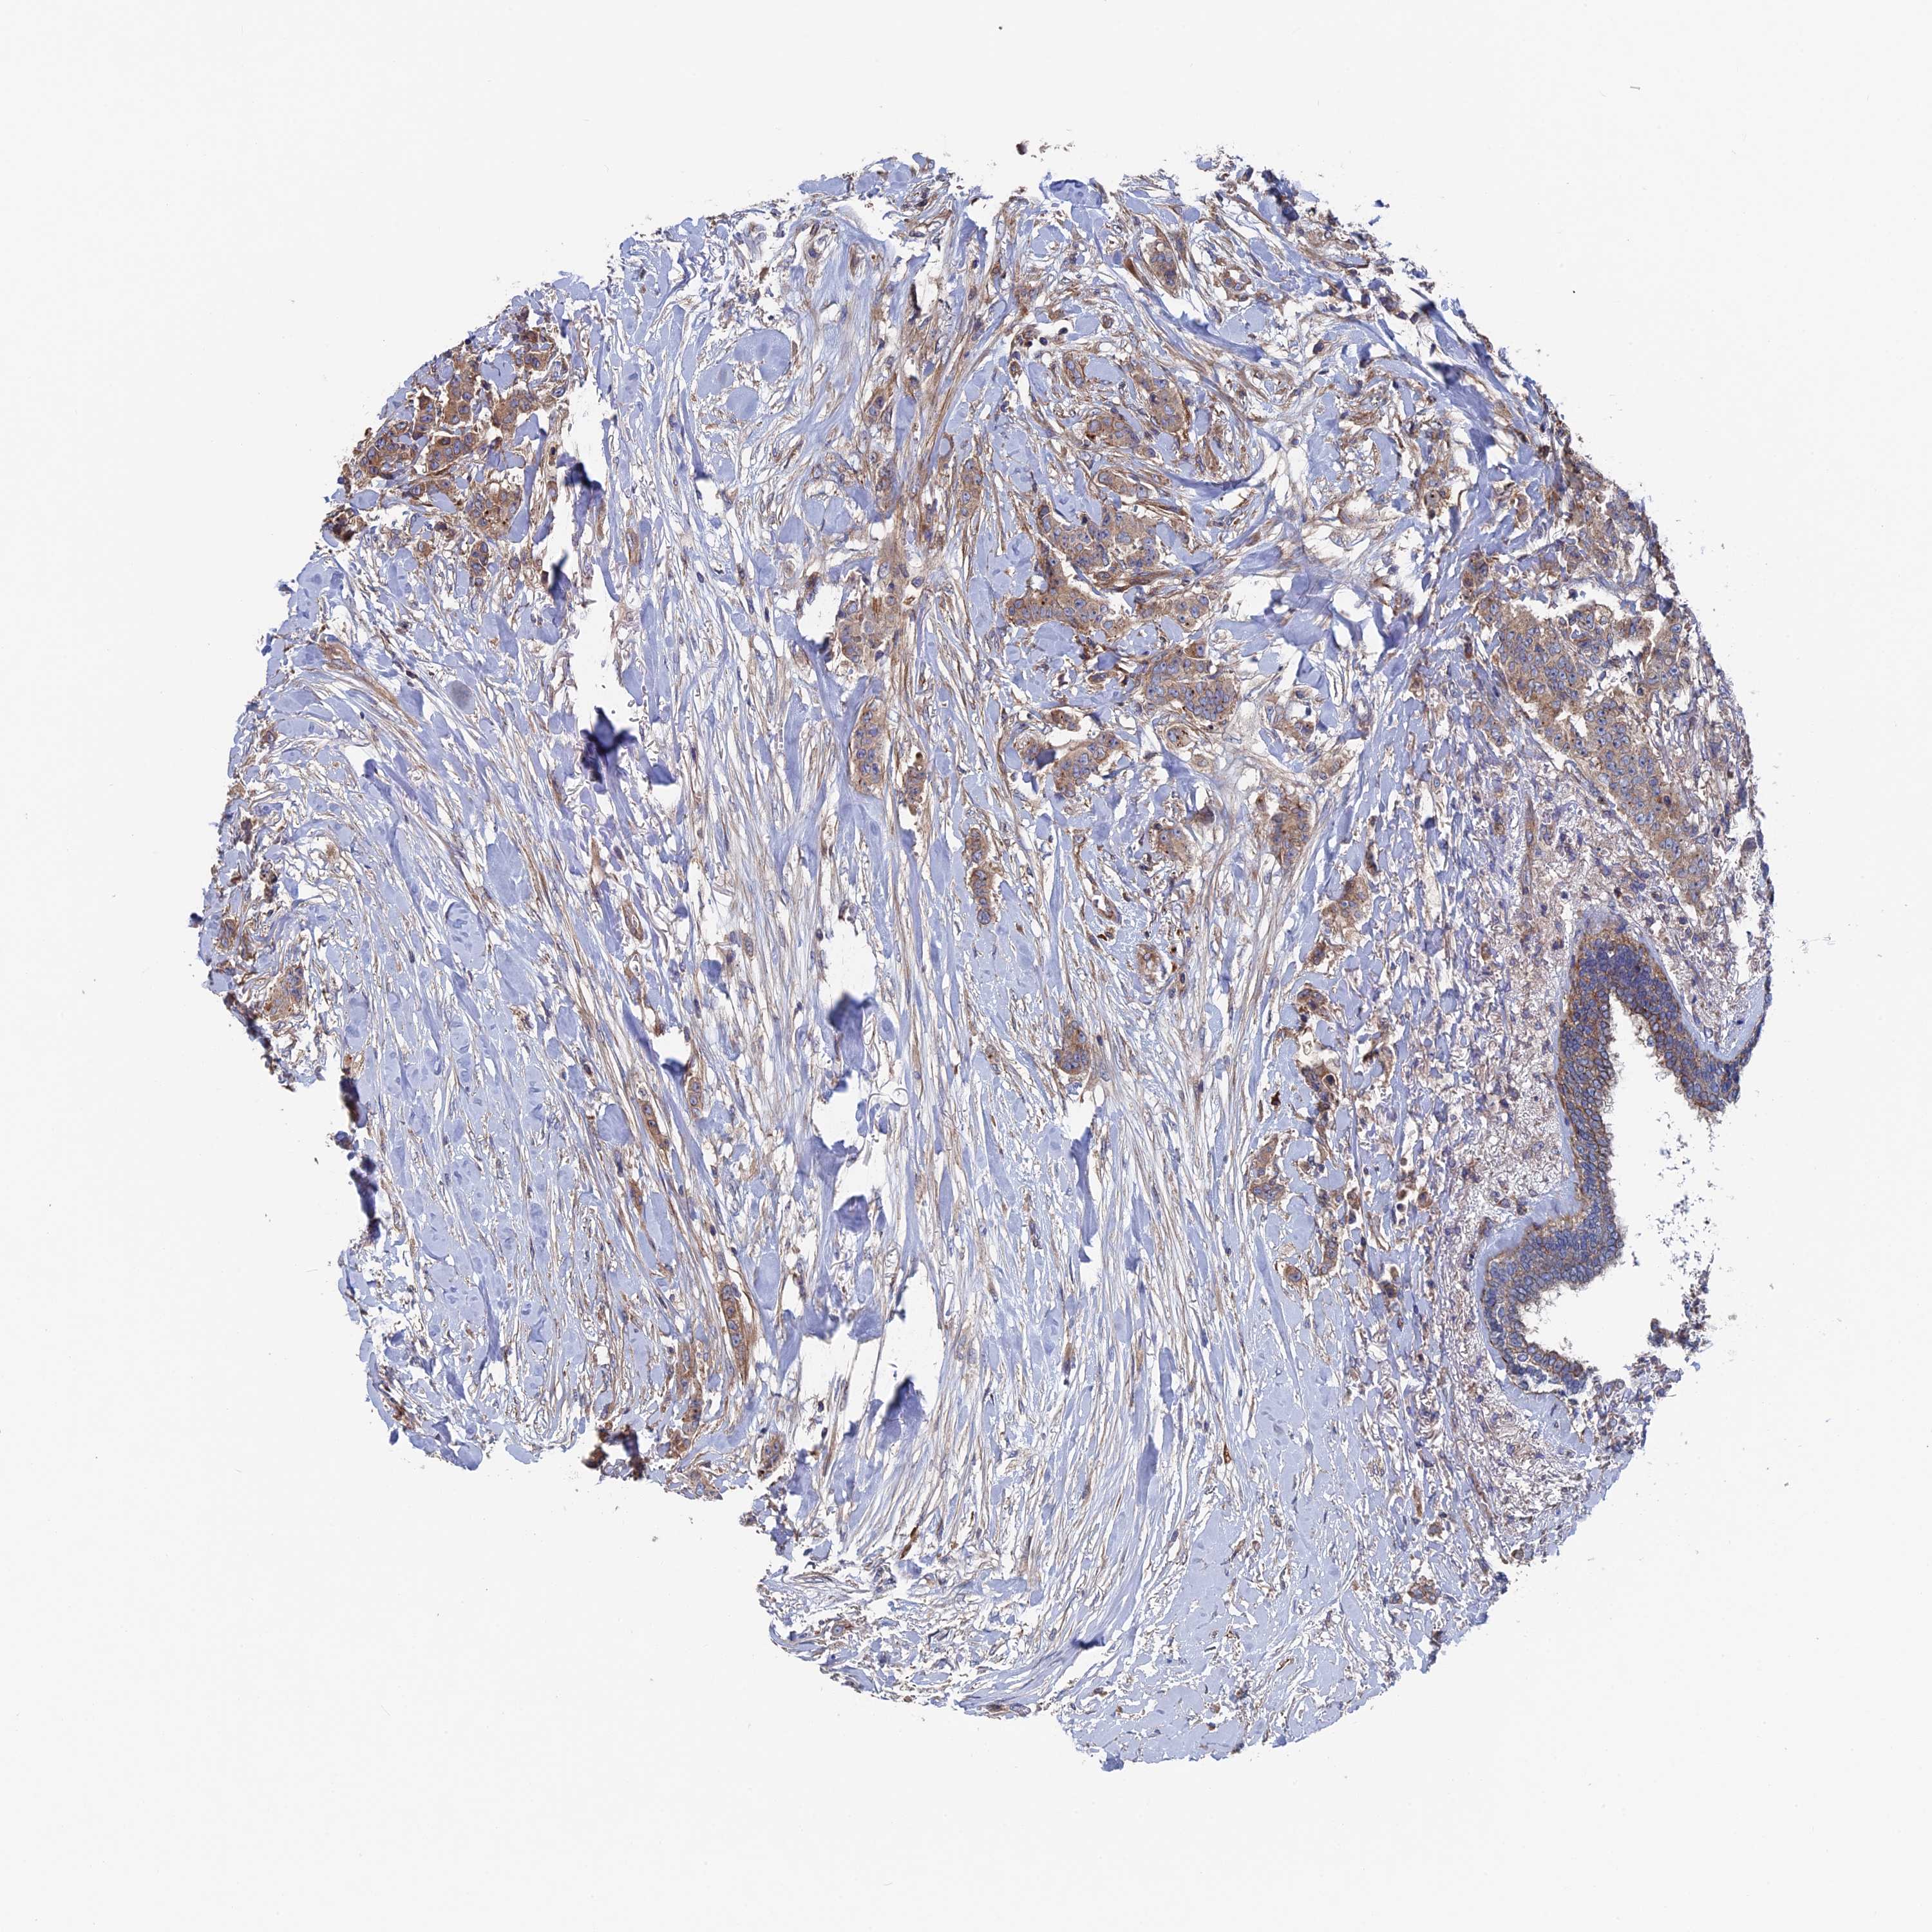

CANCER BREAST CANCER Show tissue menu

BRCA TCGA BRCA VALIDATION PROTEIN EXPRESSION

ANTIBODIES

AND

VALIDATION